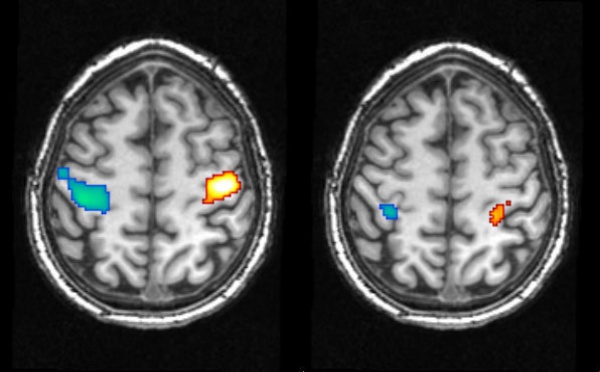

Científicos miden por vez primera el contenido de los sueños - 03/11/2011

La capacidad de soñar es un aspecto fascinante de la mente humana. Sin embargo, la manera en que se forman tanto las imágenes como las emociones que experimentamos tan intensamente cuando dormimos sigue siendo un misterio. En un estudio realizado en la Sociedad Max Planck de Alemania, un equipo de científicos ha conseguido registrar la actividad cerebral durante el sueño, y relacionarla con contenidos oníricos específicos. Los resultados demuestran que, cuando actuamos en los sueños, la actividad neuronal del cerebro es similar a la de la vigilia.